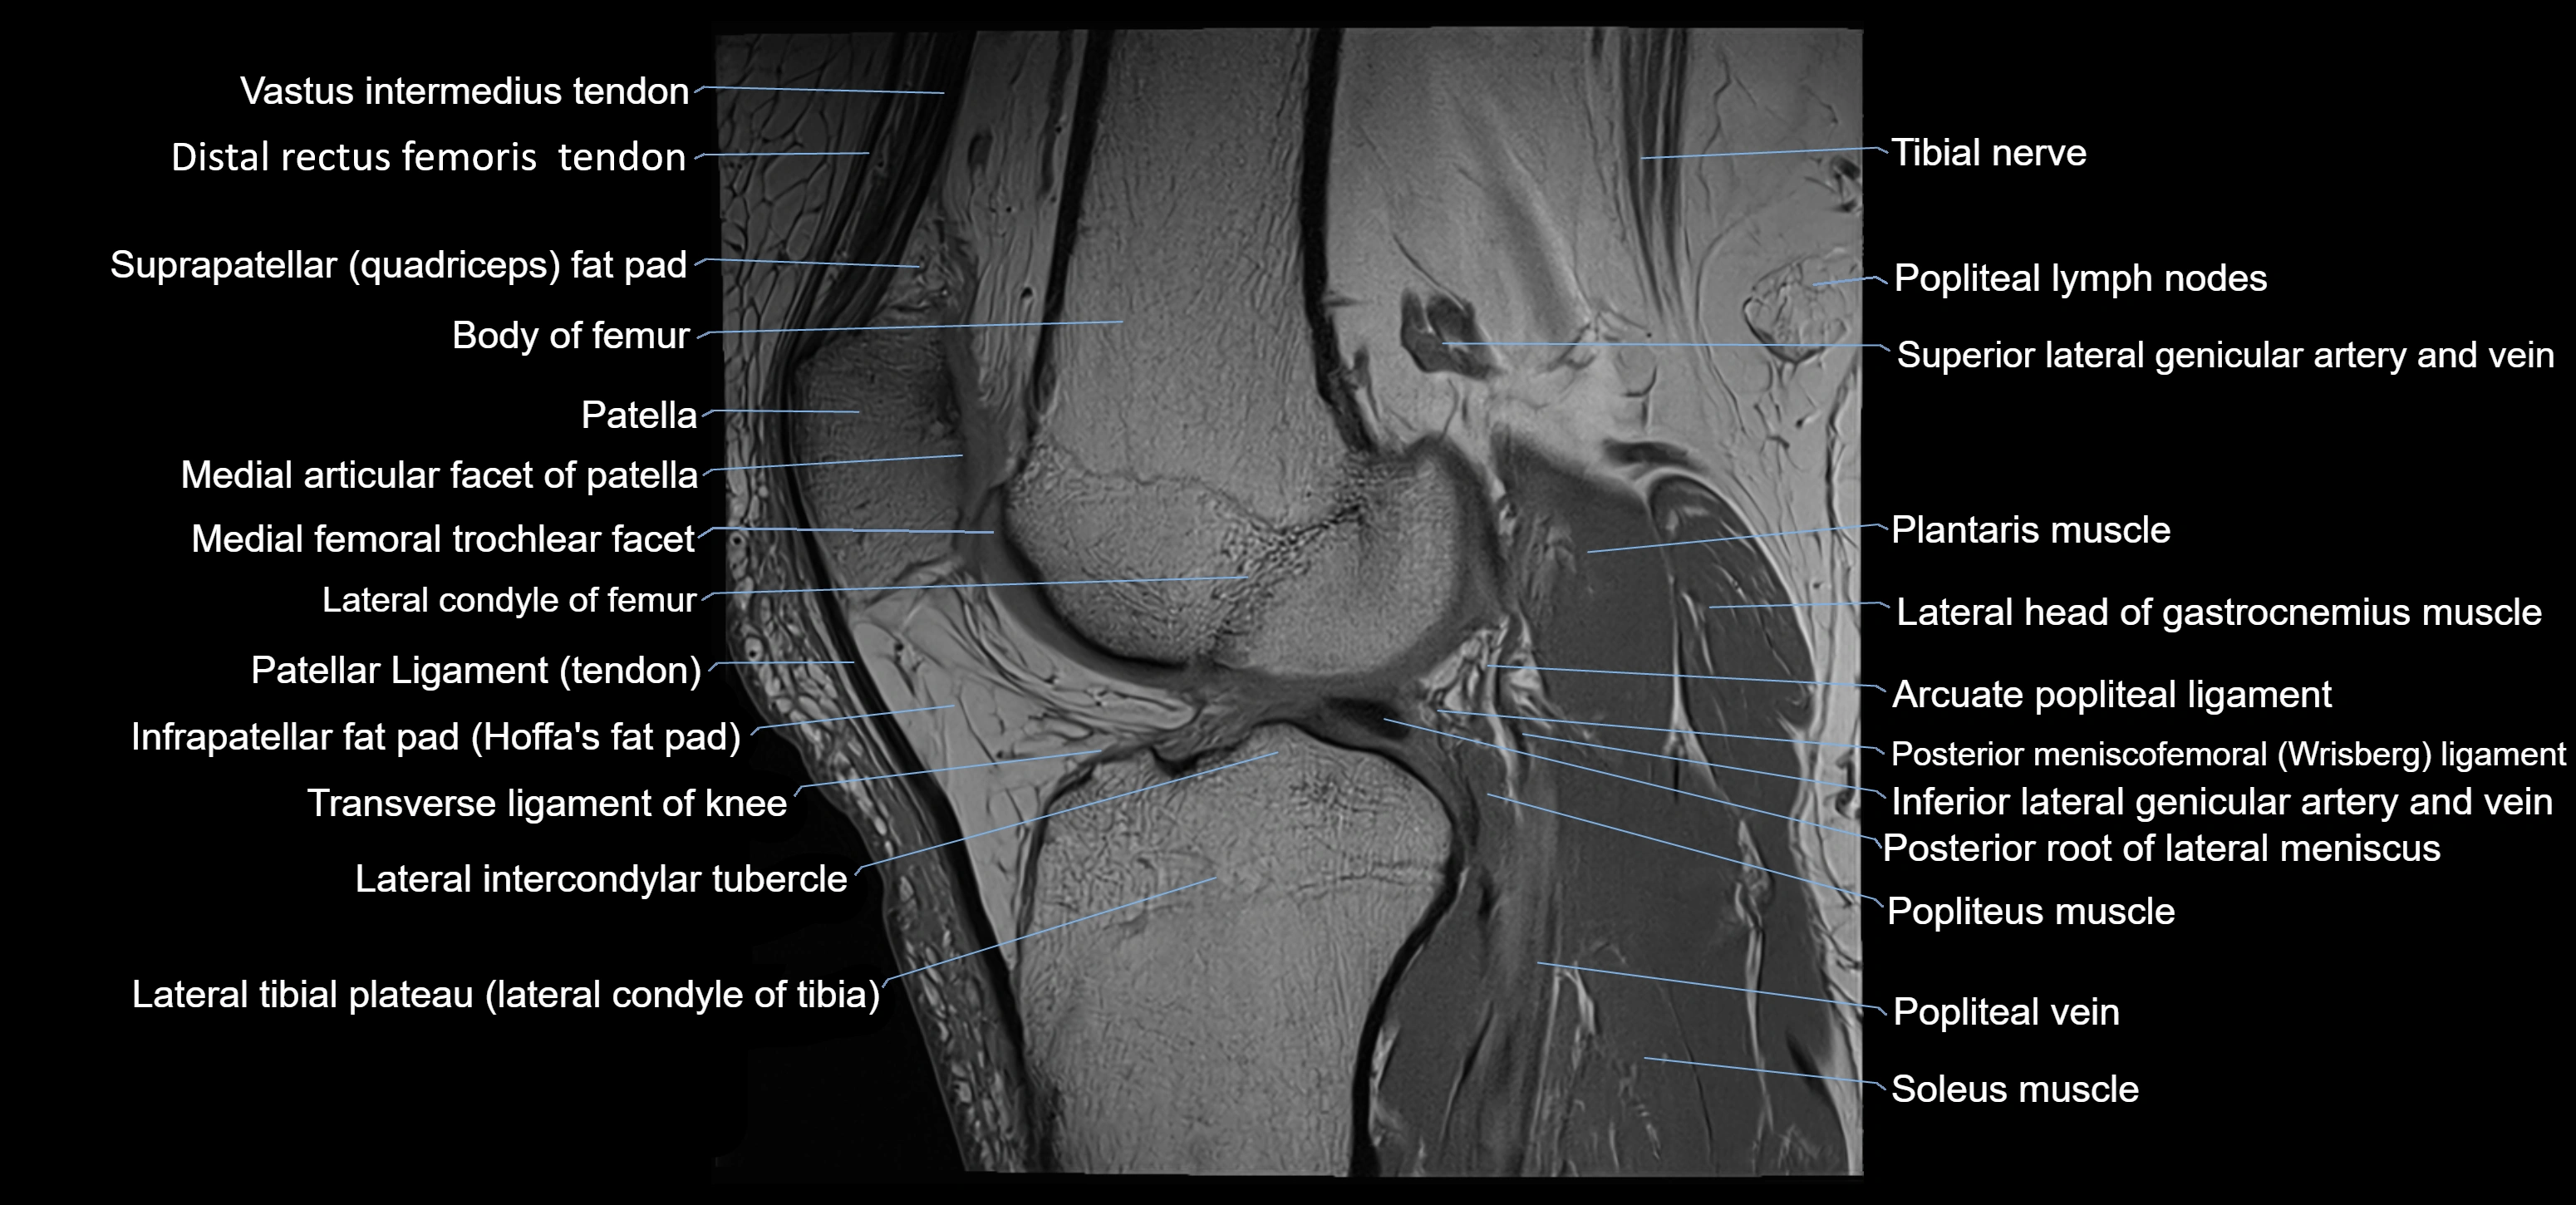

- Anterior horn of lateral meniscus

- Anterior root of lateral meniscus

- Body of femur

- Distal quadriceps femoris tendon

- Distal rectus femoris tendon

- Distal semitendinosus tendon

- Infrapatellar fat pad

- Lateral articular facet of patella

- Lateral condyle of femur

- Lateral condyle of tibia

- Lateral head of gastrocnemius muscle

- Lateral intercondylar tubercle

- Lateral tibial plateau

- Medial articular facet of patella

- Oblique popliteal ligament

- Patellar tendon (patellar ligament)

- Plantaris muscle

- Popliteal artery

- Popliteal lymph nodes

- Popliteal vein

- Popliteus muscle

- Popliteus tendon

- Posterior meniscofemoral ligament

- Posterior root of lateral meniscus

- Soleus muscle

- Superior lateral genicular artery

- Superior lateral genicular vein

- Suprapatellar fat pad

- Tibial nerve

- Transverse ligament of knee